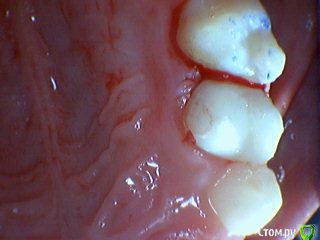

Давлетшин Опубликовано 29 декабря, 2017 Поделиться Опубликовано 29 декабря, 2017 (изменено) Друзья. Расскажите, не поменялось ли ваше отношение к пульпотеку и пр.Почему пломбы поверх пульпотеку такие ужасно жёлтые? Что сделать можно. Или что я делаю не так? "Друзья" так приятно перед новым годом. К пульпотеку не поменялось (устраивает вполне) , к пульподенту скептическое отношение, хоть и тоже работаю. Пломбы сразу желтые или через полгода - год- два? Очень тяжело что то советовать он лайн не видя как человек работает. В фото первая цифра пациент, вторая-третья номер зуба, четвертая порядок фото. Я после наложения пульпотека , стараюсь убрать излишки, или аккуратно на устья каналов накладываю, в пульповую камеру СИЦ, и сверху пломбу, Убрать излишки и со стенок, аккуратно в том числе и бором. В третьем клиническом случае, неудача. Зуб удалил сам же через 3 месяца. причину вижу в том что на рентгене не увидел (или так сделали снимок?) вертикальный тип рассасывания практически до бифуркации., может и потому что ребенок ОЧЕНЬ плохо сидел. За фото не пинайте сильно, не инстаграмм все таки,да и тяжело ребенка лечить и фотки делать. или наоборот пинайте может лучше начнем фоткать. P.s. Добавлю протокол как лечу с пульпотеком, хр.фибр.пульпит1. анестезия2. кофер ( если дает)3. раскрытие кариозной и пульповой камеры4. удаление коронковой пульпы маленьким эскаватором, я стараюсь "отрубать" пульпу5. остановка кровотечения сухим ватным шариком, 0,5-1-2 минуты6. пульпотек на устья7 СИЦ в пульповую камеру8 со стенок остатки пульпотека соскребаю бором фиссурным , цилиндрическим, там же фальц9. Пломба. может что то и зыбыл ну и оценка только позитивная перед НГ Изменено 29 декабря, 2017 пользователем Давлетшин 2 Ссылка на комментарий